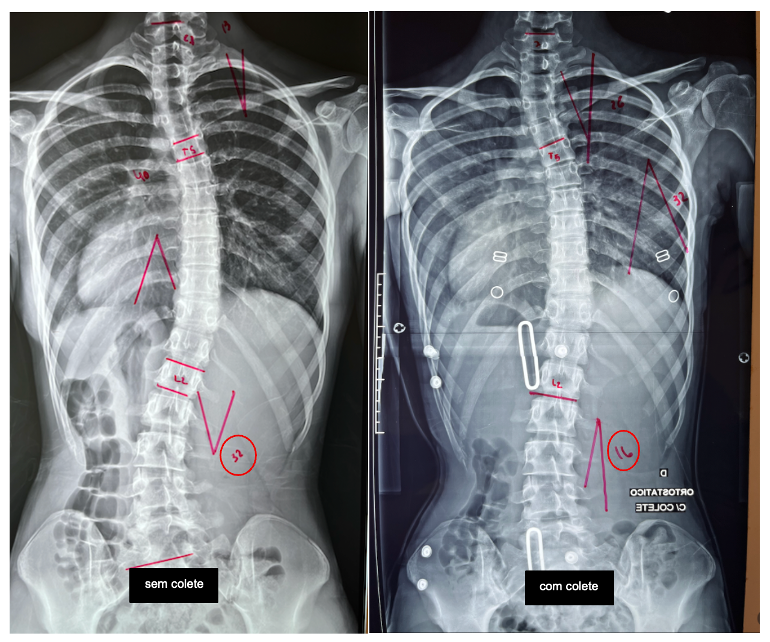

Para pacientes com curvas de maior risco, especialmente aqueles que ainda estão em crescimento, o uso do colete ortopédico mostrou-se eficaz para reduzir a progressão da escoliose até o limiar cirúrgico.

Notamos que a evidência científica mais robusta nesse contexto veio do estudo multicêntrico BrAIST (Bracing in Adolescent Idiopathic Scoliosis Trial), publicado no New England Journal of Medicine em 2013. Esse estudo demonstrou uma relação dose–resposta clara: quanto maior o tempo diário de uso do colete, maior a chance de sucesso em evitar a progressão da curva para indicação cirúrgica.

Além do colete, os exercícios fisioterapêuticos específicos para escoliose (PSSE) têm papel complementar. Estudos indicam que esses exercícios podem ajudar no controle postural, na função e, em situações selecionadas, na redução do risco de progressão.

As diretrizes da SOSORT, publicadas em 2016, sintetizaram as evidências disponíveis e propuseram recomendações baseadas no nível de risco, integrando observação, exercícios específicos e uso de colete de forma individualizada.